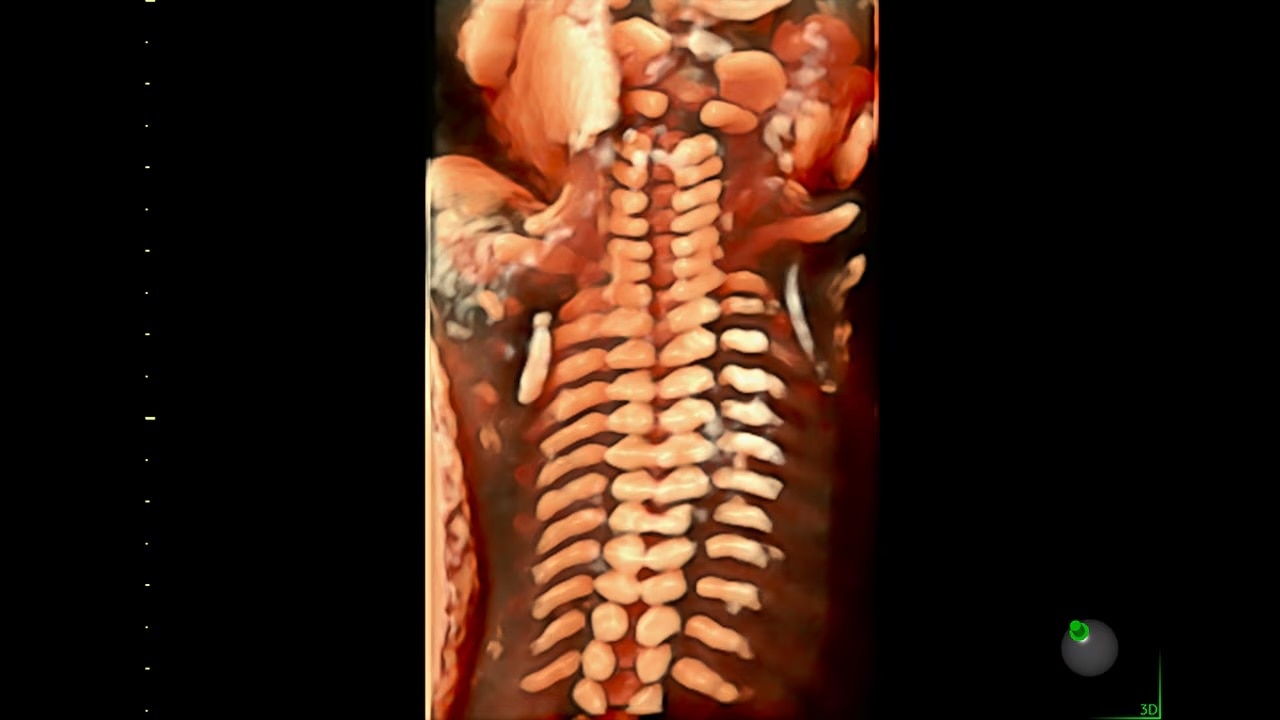

Reduce keystrokes by 83% with 3D Spine Trace